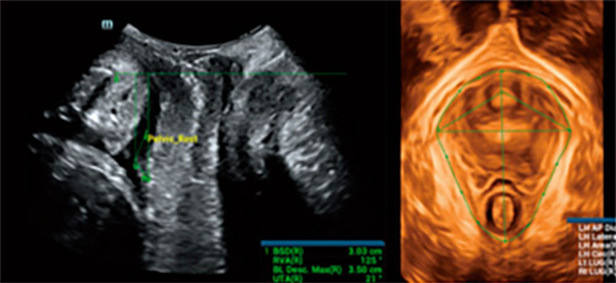

Mindray, sonografi uzmanlar?n?n karma??k pelvik taban muayenelerinde standartla?t?r?lm?? kesitleri ve ?l?Þmleri h?zl?ca elde etmesine ve te?his verimlili?ini art?rmas?na yard?mc? olmak i?in, ak?ll? bir taban ultrason ??zÞmÞ olan Smart Pelvic'i geli?tirdi. Tam pelvik ?l?Þmleri otomatik olarak yapabilir ve levator hiatusun otomatik 3B g?rÞntÞlemesiyle birlikte, uzunlamas?na ?ap, enine ?ap, levator hiatus alan? ve levator Þretra bo?lu?unun boyut ?l?Þmlerini sunar. Sonografi uzmanlar?, birka? basit etkile?imde do?ru de?erlendirme yapmak i?in kapsaml? klinik veriler elde edebilir, geleneksel muayenelerin yaln?zca 1/3âÞ kadar sÞre kullan?l?r. Ayr?ca Mindray, farkl? prob tÞrlerini ve standartla?t?r?lm?? ?al??may? destekleyen Þ? temel endÞstriyel standart sunar.

Smart Pelvic